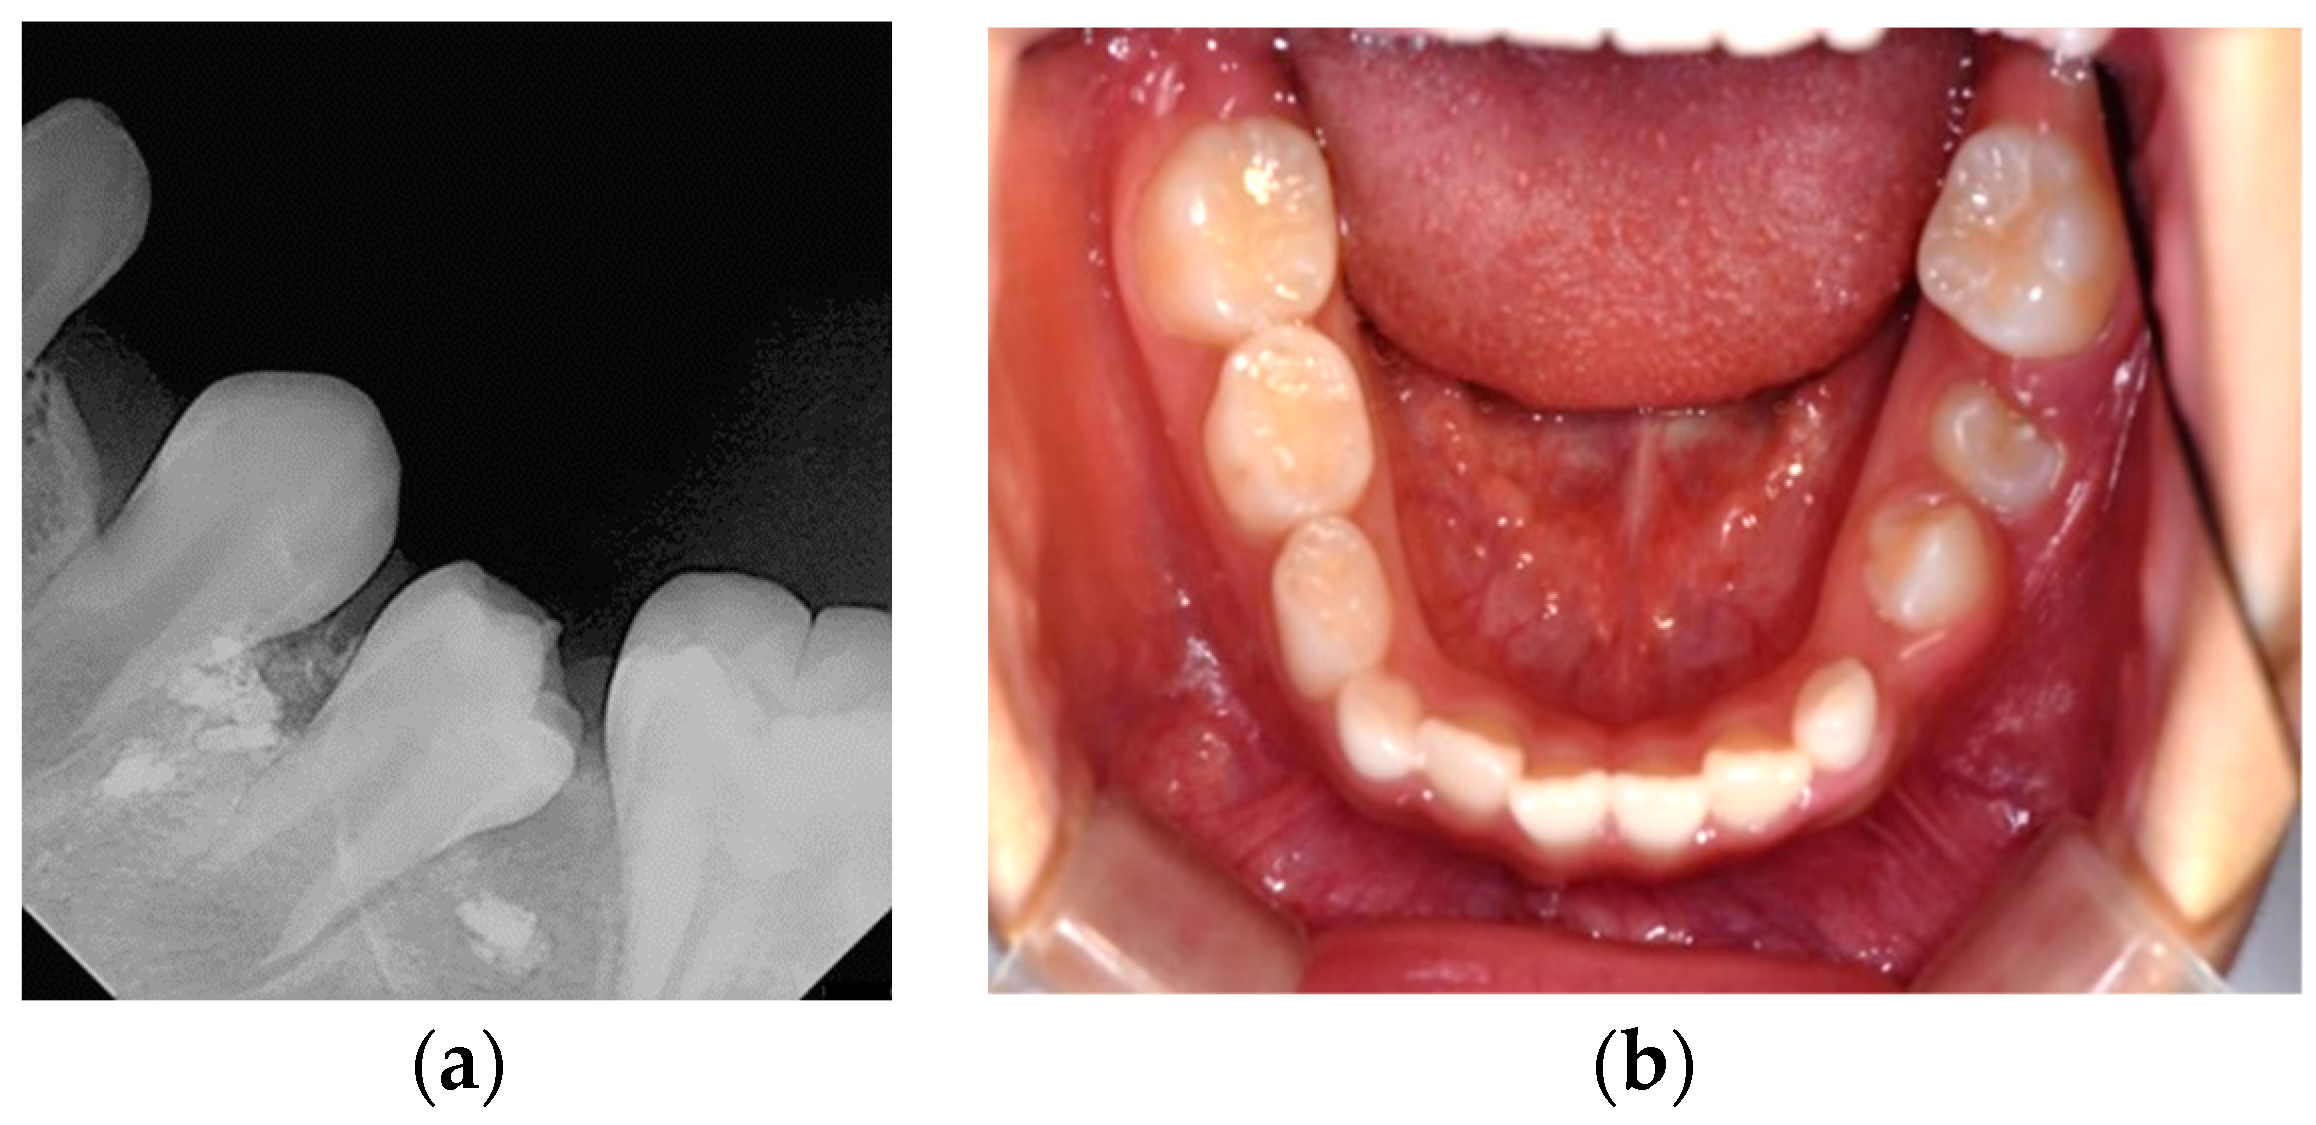

Six months after treatment, the cyst size was significantly reduced, and the premolars had erupted (Figure 5). Thirty months after treatment, the extruded canal filling material remained around the roots of the erupted left mandibular premolars (Figure 6). The patient showed no clinical symptoms.

Figure 5.

Six months after marsupialization: (a) periapical radiograph; (b) intraoral photo. Left mandibular premolars have erupted and extruded canal filling materials still exist.